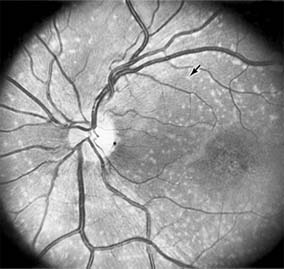

Central serous chorioretinopathy is characterized by serous detachment of the sensory retina as a consequence of focal leakage of fluid from the choriocapillaris through a defect in the retinal pigment epithelium (Figures 10-2 and 10-3). This disease typically affects young to middle-aged men and may be related to life stress events. Most patients present with the sudden onset of blurred vision, micropsia, metamorphopsia, and central scotoma. Visual acuity is often only moderately decreased and may be improved to near-normal with a small hyperopic correction.

Figure 10-2

Figure 10-2: Central serous chorioretinopathy with sensory retinal detachment (arrows) extending into the fovea.

Figure 10-3

Figure 10-3: Fluorescein angiogram of central serous chorioretinopathy shows active disease with both a retinal pigment epithelial detachment (small arrows) and a sensory retinal detachment (large arrows). Two foci of inactive disease (open arrows) are also present.